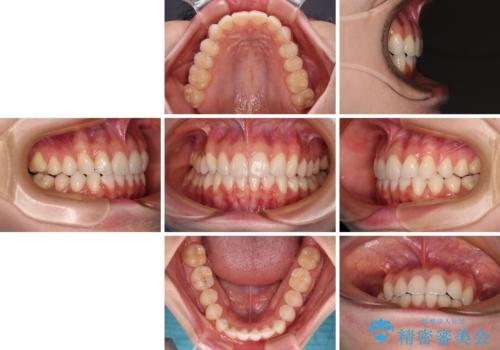

前歯のデコボコと深い咬み合わせ インビザラインできれいに改善

- 前歯のデコボコと下の前歯が隠れてしまう咬み合わせを気にして来院された患者様です。

インビザラインによる上下歯列の拡大と、IPR(歯と歯の間を削る)にるスペースの獲得により、口元のデコボコとディープバイトを改善することとしました。